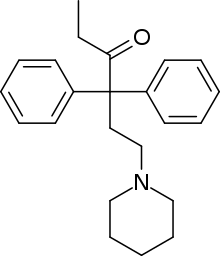

Open chain opioids

Amidones

- Dextromethadone

- Dipipanone

- Isomethadone=

- Levoisomethadone

- Levomethadone

- Methadone

- Methadone intermediate

- Normethadone

- Norpipanone

- Phenadoxone (heptazone)

Structures